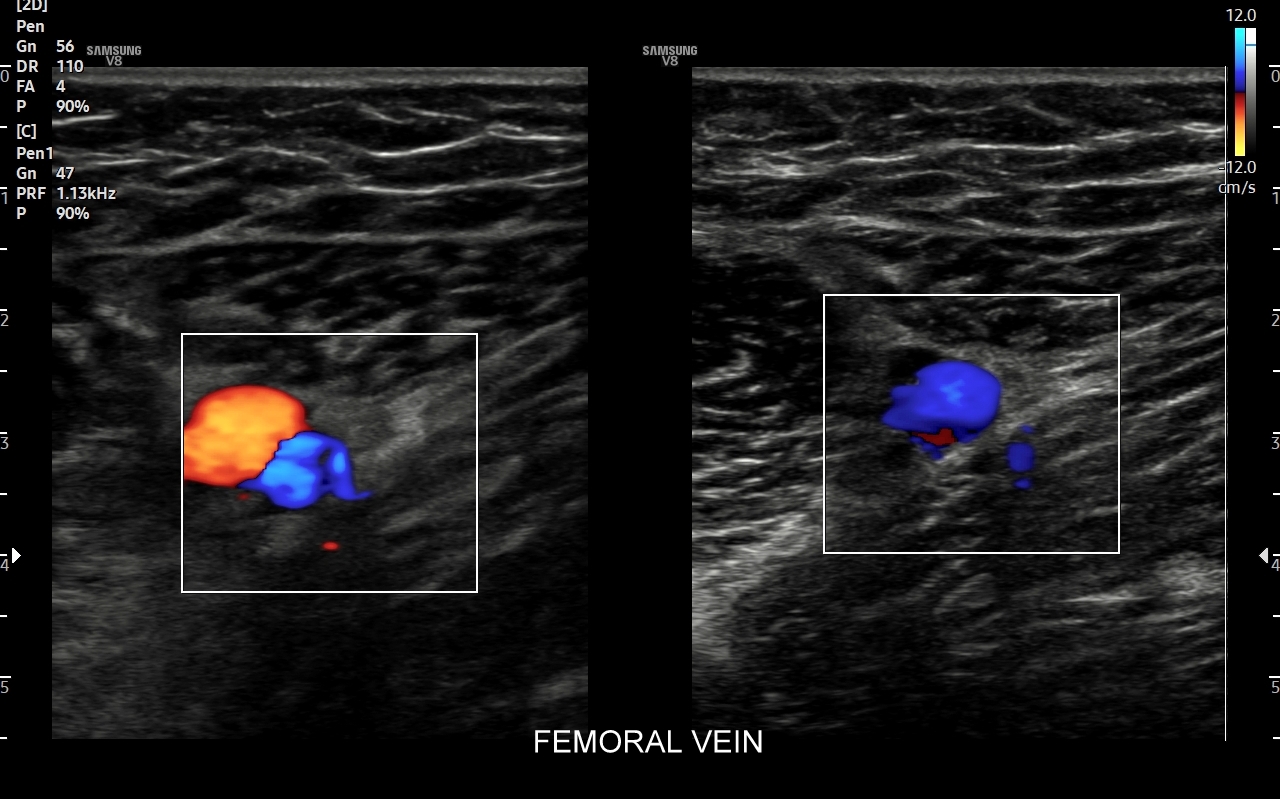

Czym jest zakrzepica żył? Zakrzepica żylna polega na powstaniu skrzepu wewnątrz naczynia żylnego i wtórnym rozwoju stanu zapalnego w okolicy naczynia. Choroba dotyczyć może układu powierzchownego żył lub żylaków, a w tym wypadku nie jest zwykle stanem niebezpiecznym; a także układu głębokiego żył, co z kolei jest stanem potencjalnie zagrażającym życiu, gdyż może sprowokować zatorowość płucną. Zakrzepica żył głębokich (ang. deep venous thrombosis DVT) częściej występuje w obrębie żył kończyn dolnych, następnie w obrębie żył biodrowych, rzadziej w żyle podobojczykowej i żyłach głębokich kończyny górnej. Przyczyny zakrzepicy żylnej są różnorodne i obejmują m. in. długie podróże, długotrwałe unieruchomienie, operacje ortopedyczne, chirurgiczne i szczękowe, urazy tkanek miękkich oraz złamania kości, genetycznie uwarunkowane trombofilie, nowotwory złośliwe, odwodnienie, infekcje miejscowe i ogólnoustrojowe. W przypadku zakrzepicy żyły podobojczykowej klasyczną jej przyczyną jest ucisk; w swojej praktyce klinicznej dr Szczepański spotkał się z zakrzepicą podobojczykową wywołaną m. in. przez ciężki plecak, wyciskanie sztangi na siłowni, czy przez uprawianie wspinaczki skałkowej. W warunkach szpitalnych zakrzepica żyły podobojczykowej lub żyły szyjnej wewnętrznej może pojawić się w wyniku zakładania cewników dożylnych. Sprawne wykrycie zakrzepicy w badaniu USG, a następnie wdrożenie odpowiedniej terapii uchronić może pacjenta przed powikłaniami ostrymi (np. zator płucny), jak i opóźnionymi (np. zespół pozakrzepowy).

Badanie USG żył kończyn dolnych najczęściej wykonywane jest w ramach diagnostyki niewydolności żył powierzchownych oraz ich objawów w postaci pajączków żylnych, żylaków kończyn dolnych, obrzęków i owrzodzeń żylnych. Kolejnym pod względem częstości wskazaniem do badania Doppler żył jest podejrzenie zakrzepicy żył głębokich kończyn dolnych, monitorowanie leczenia zakrzepicy oraz ocena jej powikłań odległych. Powikłaniem nieleczonej zakrzepicy żył głębokich może być zespół pozakrzepowy manifestujący się masywnymi obrzękami kończyny i zaburzeniami troficznymi. Badanie USG Doppler żył kończyn dolnych często uzupełniane jest oceną układu żył centralnych w miednicy i jamie brzusznej. W tych obszarach również pojawiać się mogą żylne zmiany zakrzepowe, niedrożności żył, a nawet zmiany nowotworowe.

Czy USG Doppler wykrywa zakrzepicę? Tak, badanie Doppler żył jest najważniejszą metodą diagnostyczną wykrywającą zakrzepicę żył głębokich i powierzchownych. W związku z faktem, iż nieleczona zakrzepica żył głębokich może być przyczyną niebezpiecznego zatoru płucnego lub utraty kończyny badanie Doppler należy wykonać jak najszybciej w każdym przypadku podejrzenia zakrzepicy.